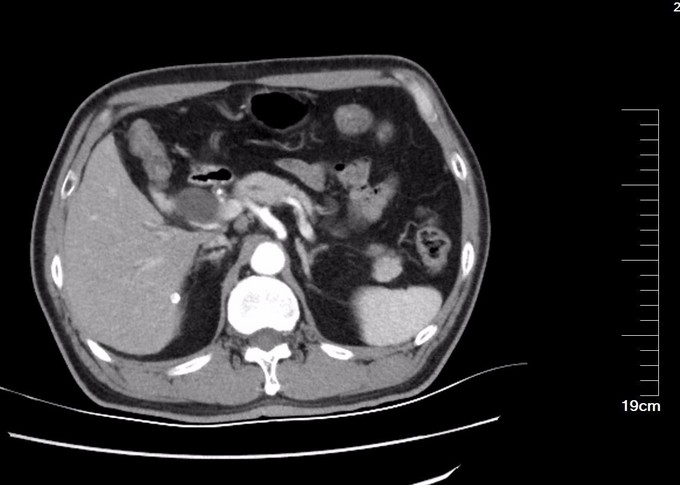

查体:全身皮肤及巩膜黄染,腹部膨隆,无胃肠型,腹软,中上腹压痛,无反跳痛,肝脾未触及,肝肾区无叩痛,肠鸣音6次/分,移动性浊音(-)。 辅查: CT:胰头部隐约见弱强化灶,局部门脉管径变细,胰头周围及腹膜后见增大淋巴结。胆总管胰腺段管壁增厚,明显强化,近端肝内外胆管扩张。胰管未见扩张。胰尾部见小囊状不强化灶,长径约8mm。MR 肝脏表面光滑,各叶比例协调,肝实质信号欠均匀。肝内外胆管普遍扩张,胆总管下段狭窄,中上段扩张,最宽处约1.8cm,胆囊壁增厚,其内信号不均。胰头部见稍长T1稍长T2信号影,境界模糊,范围约2.9cm×1.5cm,胰腺体尾部见长T1长T2信号结节影,大小约8mm×3mm,胰管轻度扩张。脾脏不大。 MRCP:肝内外胆管普遍扩张,胆总管下段狭窄,中上段扩张,宽约1.8cm,胆囊轮廓不清。胰腺体尾部见长T2信号结节影,大小约8mm×3mm,胰管扩张,胰腺头部主胰管狭窄。血清胆红素190.1umol/L,以直接胆红素升高为主。

诊断: 胰头占位 恶性可能大 治疗:全麻下手术探查:肝脏於胆改变,无转移结节,腹壁及盆腔未见癌转移,胰头略增大,切开kocher筋膜,游离十二指肠降段,显露胰头后方,触及胰腺钩突2.5×2.0cm质硬肿物,界不清,胆囊无明显增大,约7×4×3cm,肝总管、胆总管全程明显扩张,直径约1.8cm,术中诊断胰腺头部占位,行胰十二指肠切除术,术中冰冻病理及术后病理证实恶性。病理镜下:癌细胞呈不规则腺样,筛网状排列,部分区域见淋巴组织。胰腺腺癌,高分化,肿物周围见少许淋巴结结构,考虑淋巴结受侵及,胃、肠、网膜未见癌,慢性胆囊炎。CD34及D2-40染色未见明显脉管癌栓,S-100染色见神经侵犯。